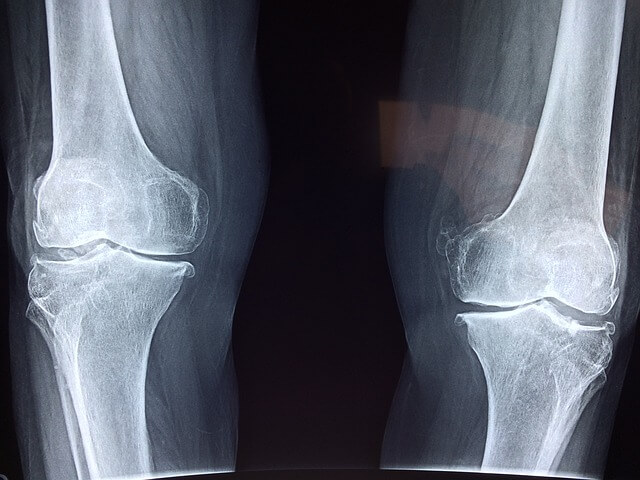

관절염이란?

관절의 염증이 생긴 상태로 염증에 의한 통증이 대표적입니다.

단순하게 관절에 통증이 있다고 모두 관절염은 아니며, 붓거나 열감을

동반해야 관절염이라고 볼 수 있습니다.

관절염은 급성인지 만성인지에 따라 구분되고 중추 관절인지 말단 관절인지에

따라 관절염의 원인을 알아내 치료를 받을 수 있습니다.

관절염의 종류

급성 관절염과 만성 관절염으로 나뉘며,

급성 관절염의 경우 간단하게 요약하자면 외상에 의해 나타나고,

뼈의 탈구나 골막골수염에 걸려 화농부가 터져

고름이 관절로 들어가서 생기는 경우 생깁니다.

만성 관절염의 경우

요산대사 장애로 인해 통풍성 관절염과 만성 관절류머티즘에 의한 것.

혹은 뼈나 관절의 노화와 외상, 혈우병, 자가면역질환인

류마티스성 관절염에 의해 생깁니다.